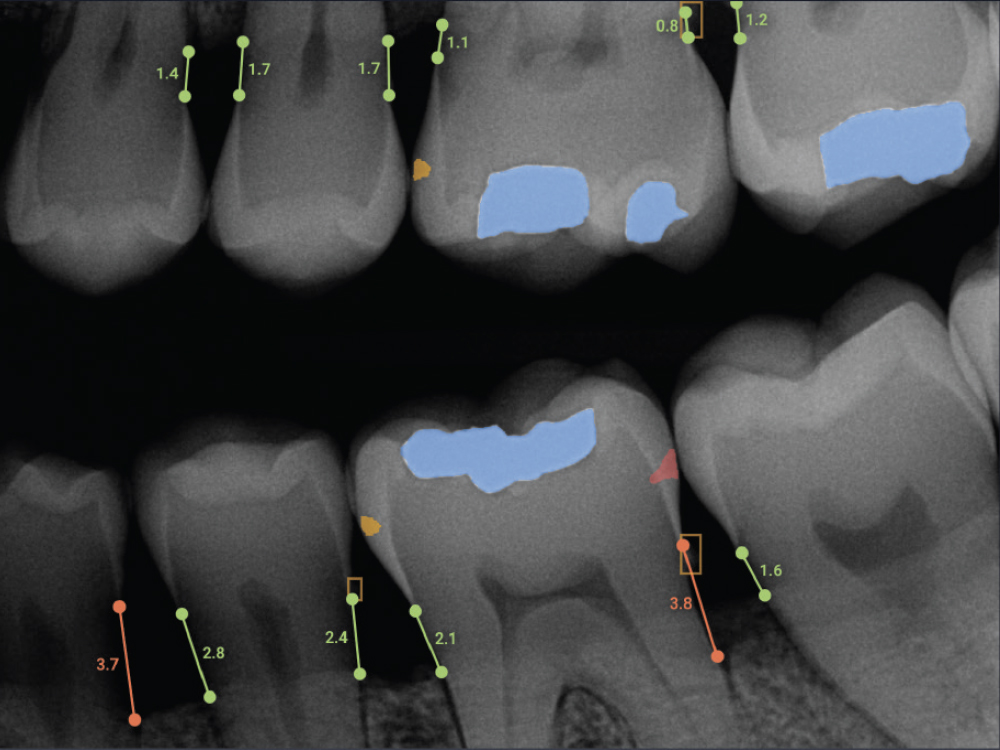

Think of Overjet AI as a highlighter for your X-rays. It is an artificial intelligence platform cleared by the FDA specifically for dental use. When we take your X-rays, Overjet’s software analyzes them instantly. It measures bone levels to the millimeter and detects cavities that might be too small for the human eye to catch easily.

Instead of just looking at a black-and-white image, Overjet adds color and measurements directly onto the screen.

Imagine we are discussing a potential issue with your gum health. Instead of using complex medical terms, we can show you the screen. Overjet overlays color-coded measurements on your X-rays. Green means healthy, while red indicates areas where bone loss has occurred.

Suddenly, the concept of “gum disease” isn’t abstract anymore. You can see exactly where the bone levels should be versus where they are. This visual clarity builds trust. You never have to wonder if a treatment is truly necessary because the evidence is right there in front of you, clear as day.